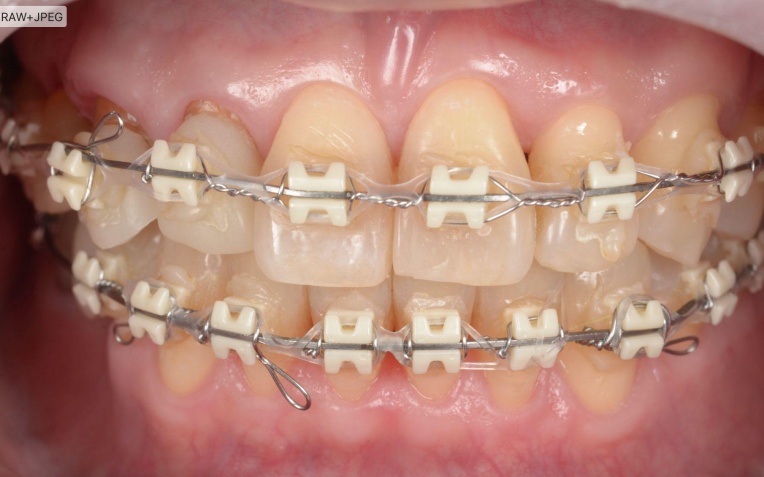

①まず、ワイヤー矯正治療で噛み合わせを整える

ワイヤーの力を使い、歯の位置を少しずつ動かしながら噛み合わせ全体を整える治療です。今回のケースでは、折れている歯を一時的に利用しながら矯正治療を進めます。

まず、ワイヤー矯正装置を用いた矯正治療を開始します。

折れている歯を一時的に利用しながら、受け口傾向にある噛み合わせが改善するよう、歯の位置を少しずつ調整していきました。

矯正治療中は定期的に来院いただき、装置の調整を行います。

歯や歯茎の状態、噛み合わせの変化を確認しながら、目標とする歯並びと噛み合わせに近づくよう治療を進めました。

治療中